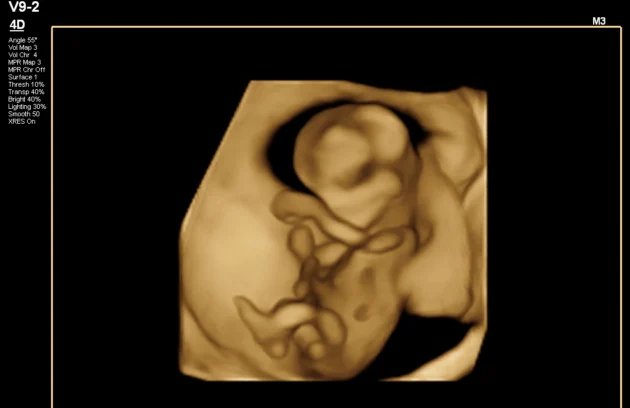

🔹 3D / 4D Ultrasound

3D/4D Ultrasound provides a clear and real-time view of your baby inside the womb. While 3D shows detailed images, 4D allows you to see live movements like smiling or yawning. It enhances bonding between parents and baby while also helping doctors assess physical development. Experience advanced 4D ultrasound in Kathmandu for a memorable and informative pregnancy journey.